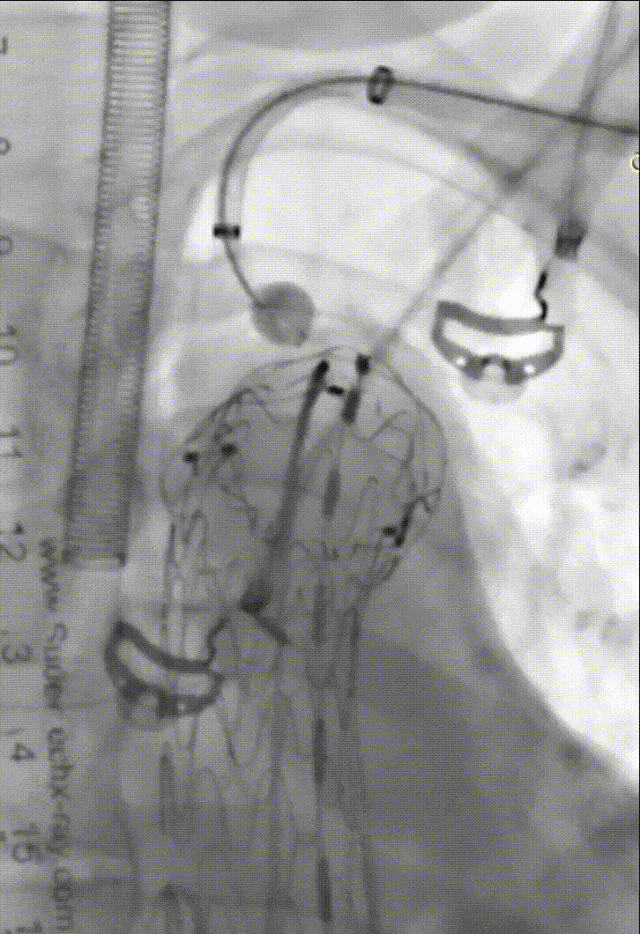

裙边烟囱技术

操作简便、手术时间短,适用于急诊、老年不耐受长时间手术患者及其他技术失败的中转或二次手术补救,小弯侧病变应用更多。但Ia型内漏风险高,即动脉壁、主体支架及分支支架形成的沟槽效应。目前,“裙边烟囱”技术在一定程度上解决了这一难题。